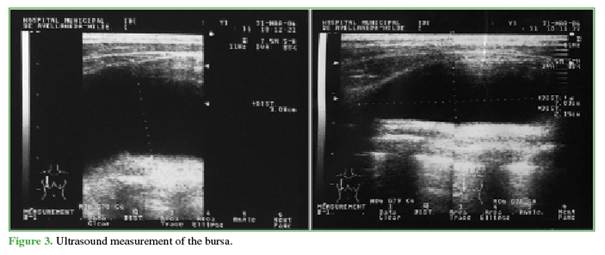

Complementary studies revealed a ventral osteochondroma near the inferior angle of the scapula (Figure 2). Computed tomography showed the typical mushroom-shaped image at approximately the level of the fifth rib and a homogeneous hypodense fluid collection measuring 16 × 5 cm. Traumatic bone lesions were ruled out. Ultrasound also demonstrated the fluid collection, measuring 150 x 30 x 80 mm (Figure 3).